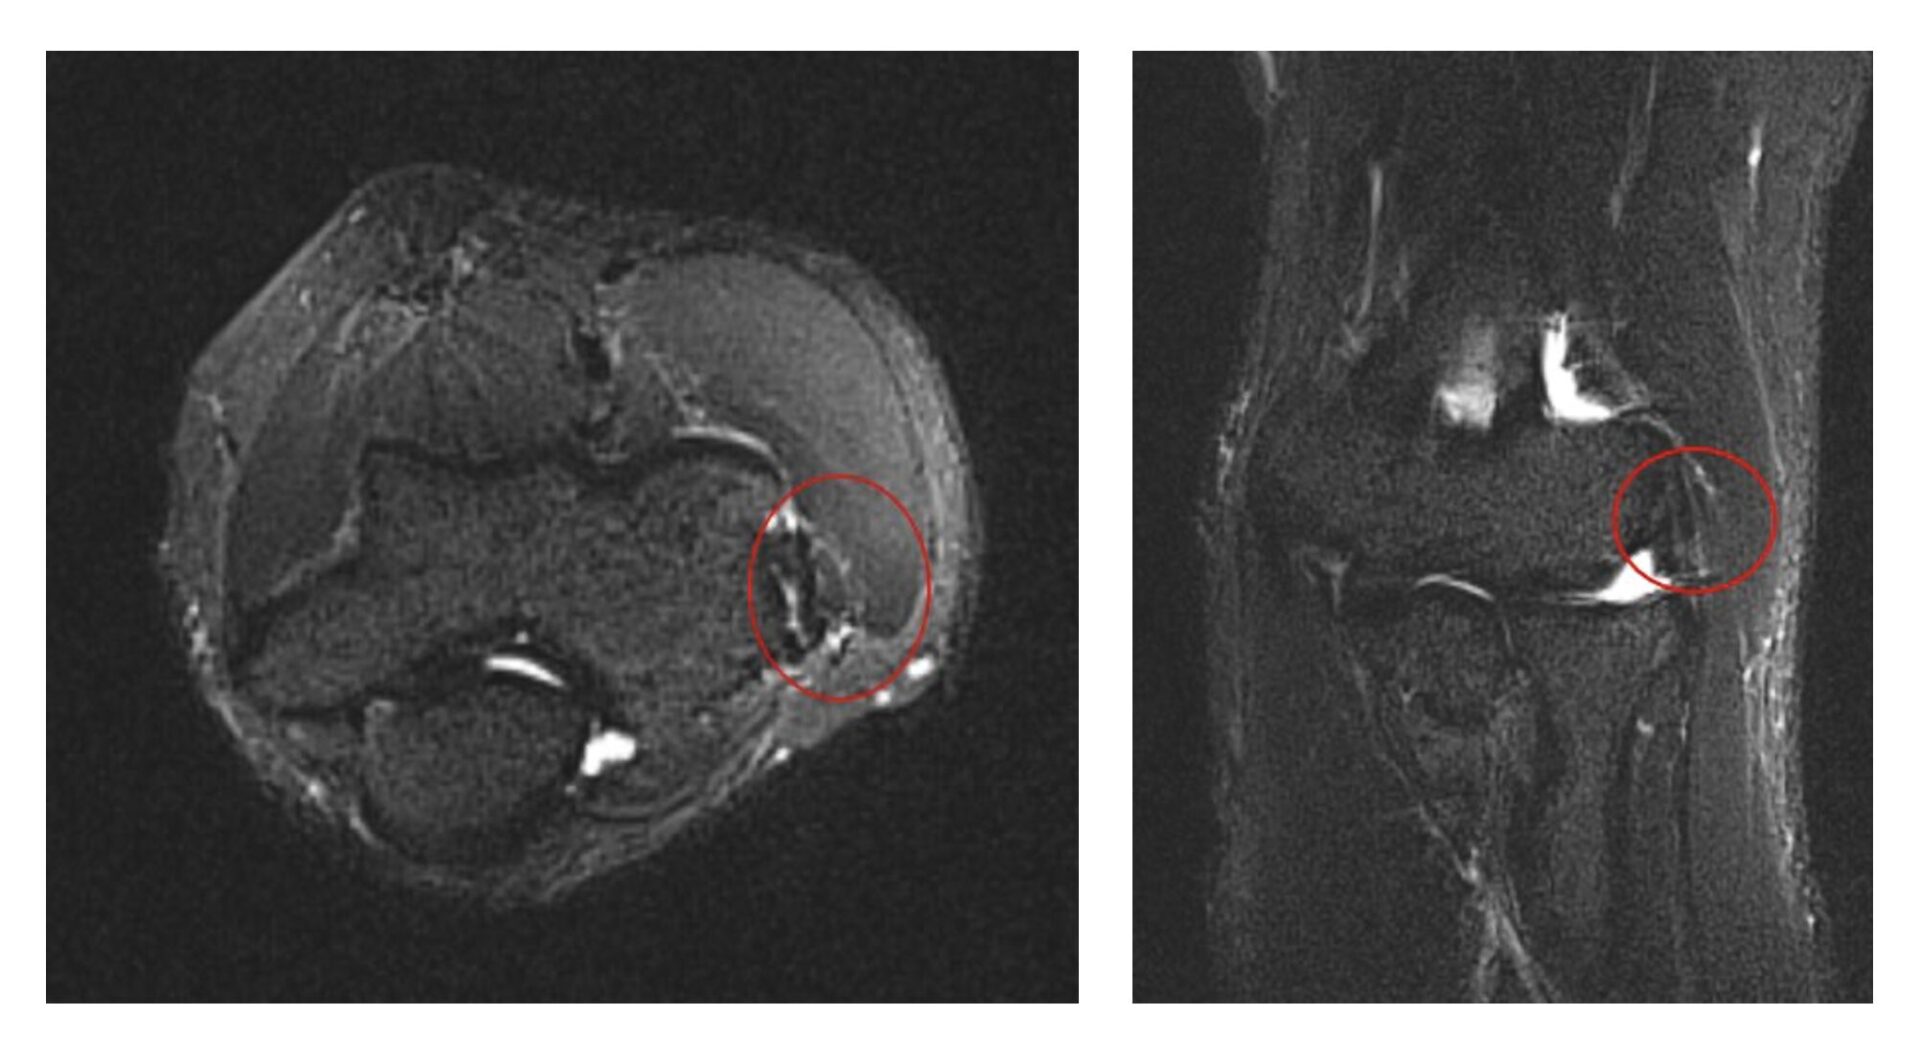

- MRI:腱の付着部に変性や損傷を確認します。その他関節内や骨、靭帯の評価も行います。

上記は実際に撮影したテニス肘のMRI画像です。